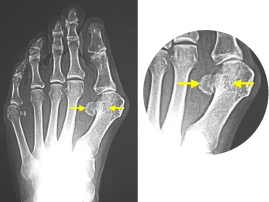

歩行困難になる、タコ・魚の目

タコ

魚の目